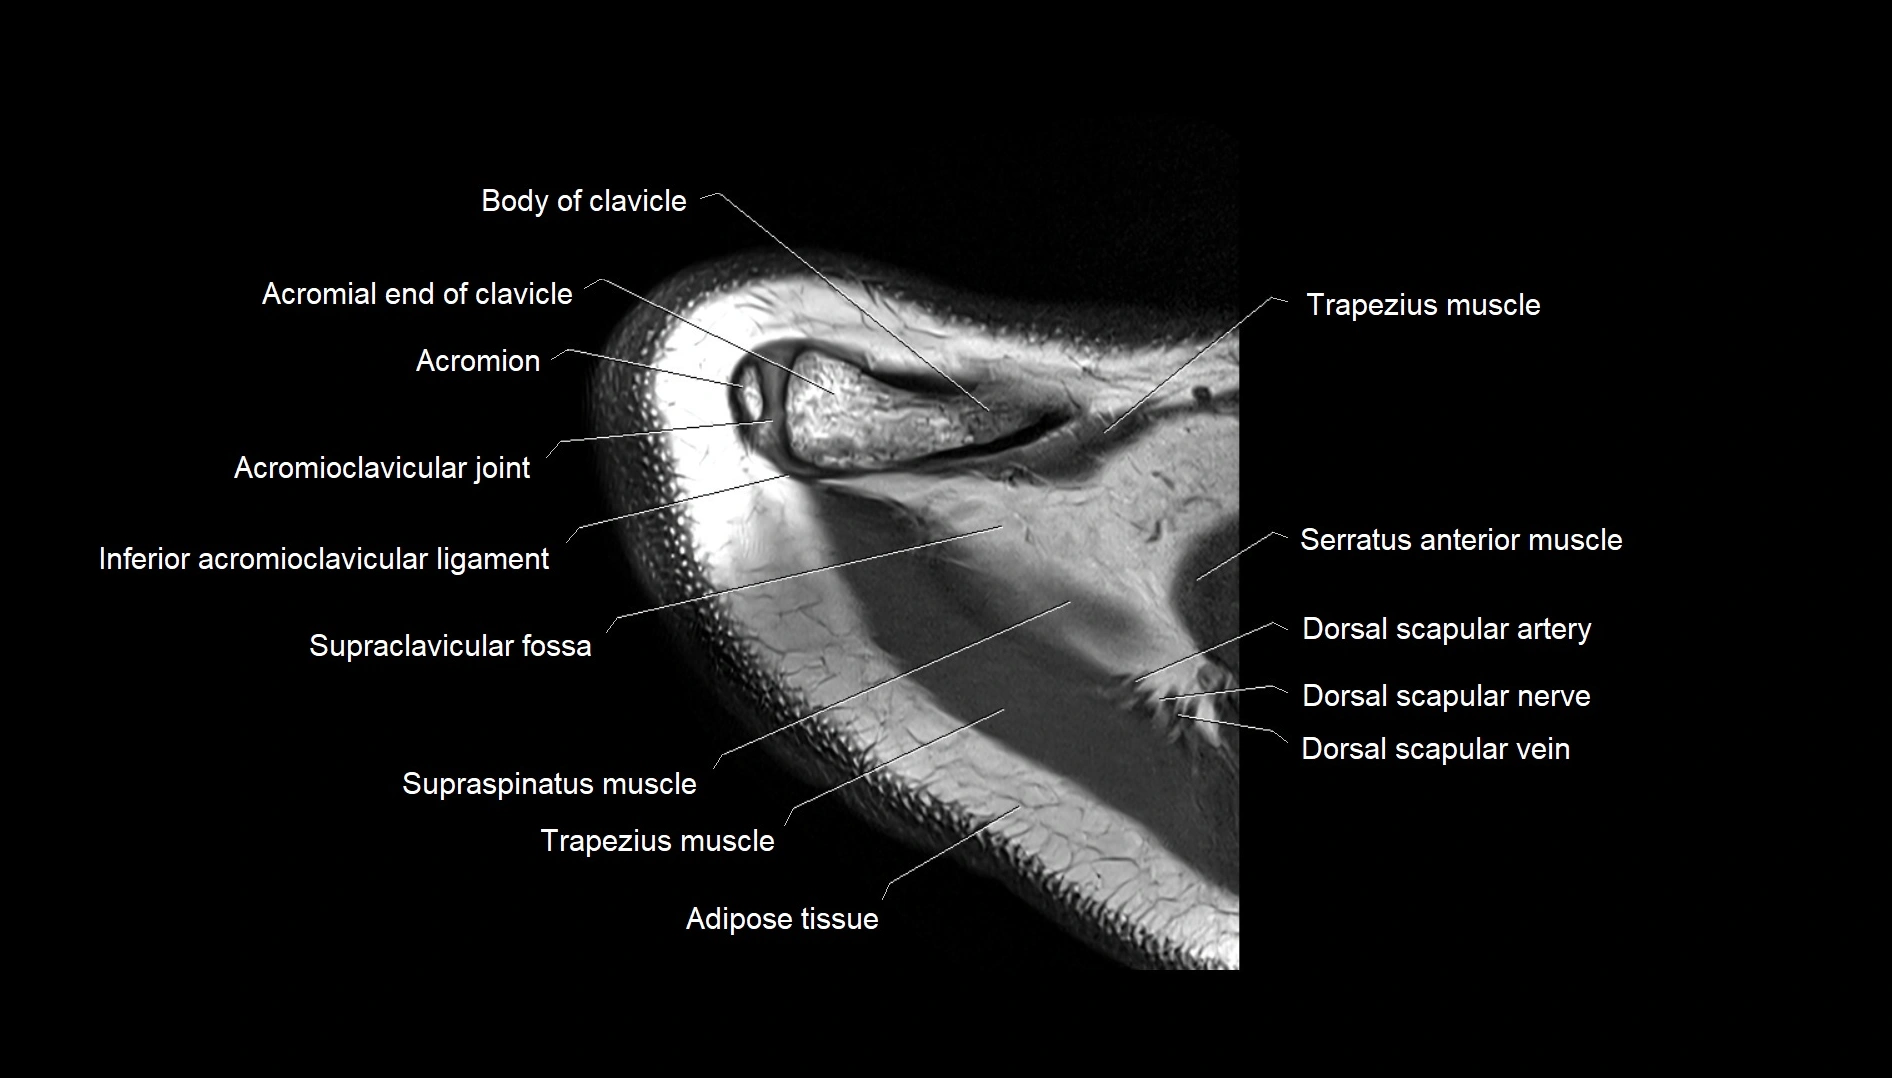

CT image

image